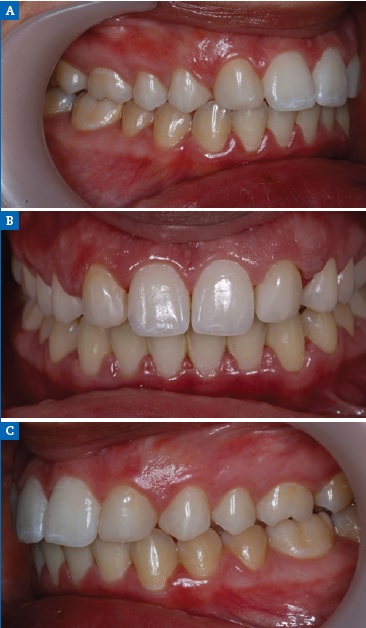

Figure 11 Case 2: Intraoral views of the (A) right, (B) frontal, and (C) left aspects after the orthodontic treatment.

A 15-year-old patient presented with unilateral MLIA and microdontia (Figure 9). The left maxillary canine erupted mesially from its normal position, while the right maxillary lateral incisor was conical. Both central incisors were tipped to the left and associated with occlusal plane canting to the left. There was also an evident Bolton’s anterior discrepancy of 74.1 % (13, 12, 11, 21, 23, 24 / 43,42, 81, 71, 32, 33) due to maxillary asymmetric agenesis, a canine in place of the lateral incisor, and a conical contralateral (Figure 10). And due to agenesis of the mandibular central incisors and the presence of correspondent deciduous teeth. After the orthodontic treatment (Figure 11), the complexity of the asymmetric case required digital smile planning (Figure 12) and a diagnosis wax-up (Figure 13) to plan and visually demonstrate the desired result to the patient.